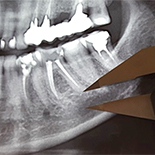

The aim of this study was to compare the reliability of panoramic radiography (PR) and cone beam computed tomography (CBCT) in the evaluation of the distance of the roots of lateral teeth to the inferior alveolar nerve canal (IANC).

100 PR and 100 CBCT images that met the selection criteria were selected from the database. In PR images, the distances were measured using an electronic caliper with 0.01 mm accuracy and white light x-ray film reviewer. Actual values of the measurements were calculated taking into consideration the magnification used in PR images (130%). Measurements on CBCT images were performed using i-CAT Vision software. Statistical data analysis was performed using R software and applying Welch’s t-test and the Wilcoxon test.

There was no statistically significant difference in the mean distance from the root of the second premolar and the mesial and distal roots of the first molar to the IANC between PR and CBCT images. The difference in the mean distance from the mesial and distal roots of the second and the third molars to the IANC measured in PR and CBCT images was statistically significant.

PR may be uninformative or misleading when measuring the distance from the mesial and distal roots of the second and the third molars to the IANC.